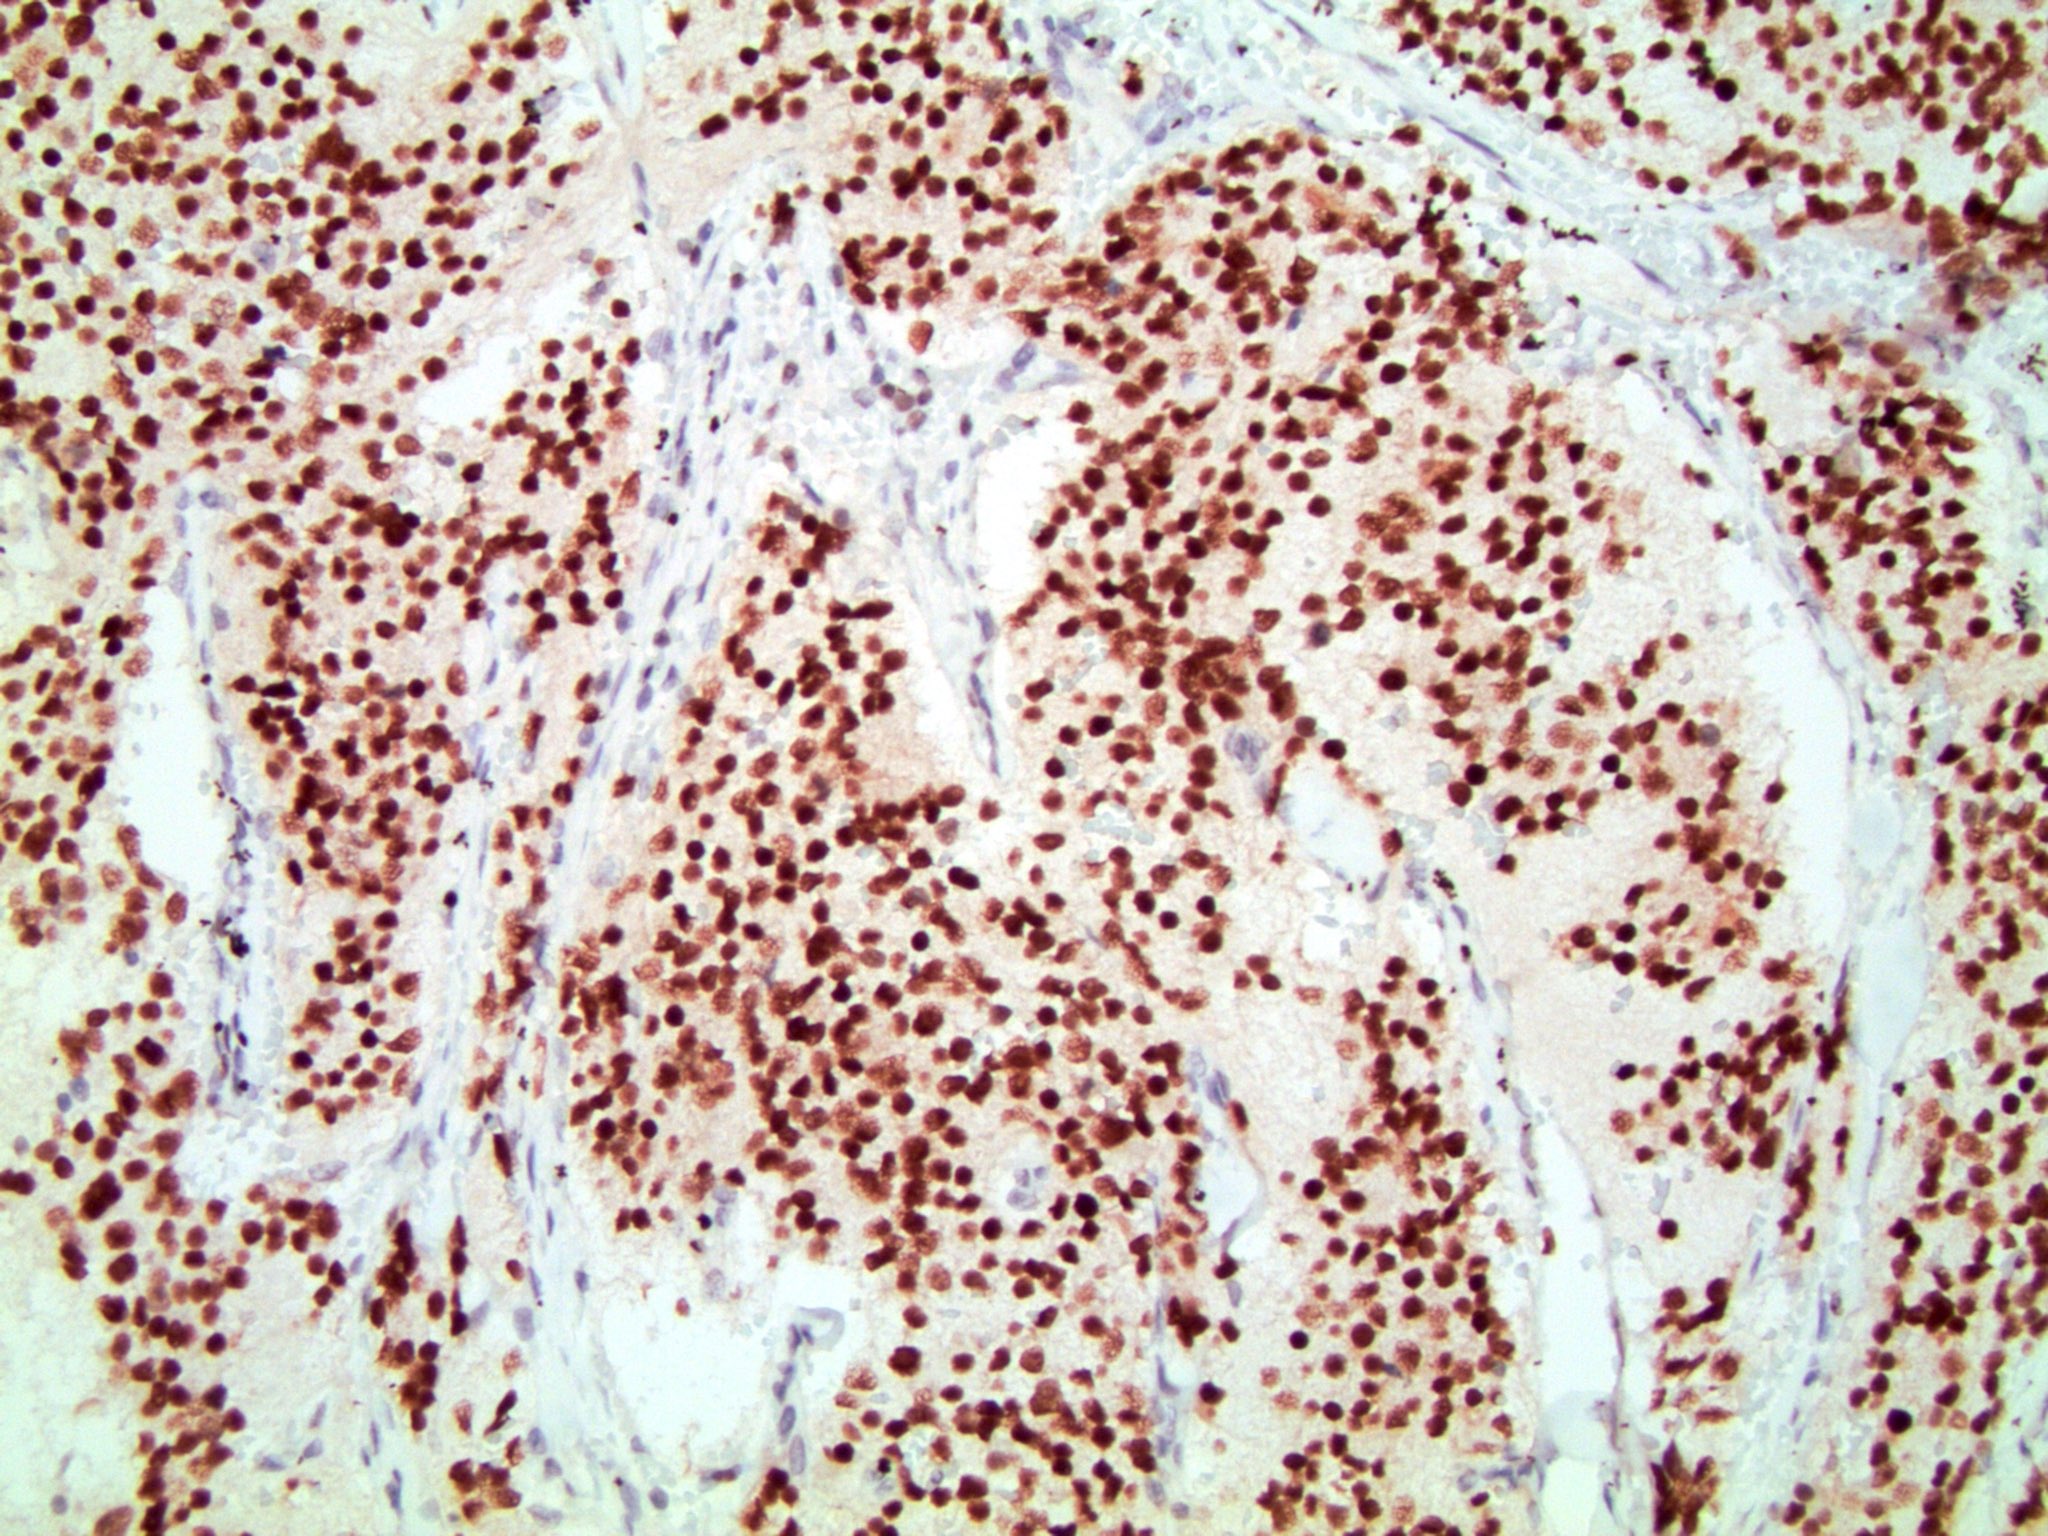

Microscopic (histologic) images

Contributed by Emily S. Reisenbichler, M.D., Andrey Bychkov, M.D., Ph.D., Maria Tretiakova, M.D., Ph.D. and Debra Zynger, M.D.

Positive staining - tumors

- Neuroblastoma (100%) (Cancer Cytopathol 2017;125:940)